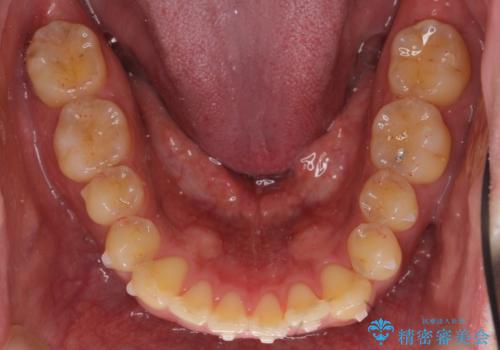

前歯のねじれを 1年かけずに矯正 インビザライン

- 前歯のねじれを主訴に来院。

インビザラインで治療しました。

前歯のねじれをセラミックで治そうとすると、抜髄といって、神経の治療が必要になる上、歯の幅も制限が出て理想的にはなりません。

保定の必要がありますが、天然歯を並べる矯正治療では、治療後の心配事が非常に少なく、保存的な処置となります。